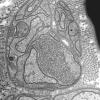

PERIPHERAL NEUROPATHY

5 AXONAL REGENERATION (7)